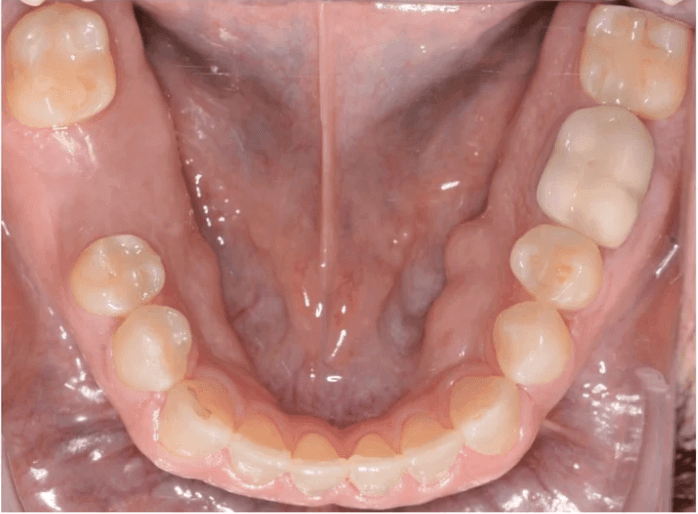

Initial treatment

INTRAORAL